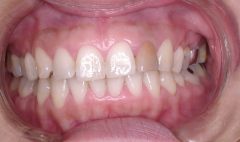

治療前 正面

上顎前歯がかぶっています